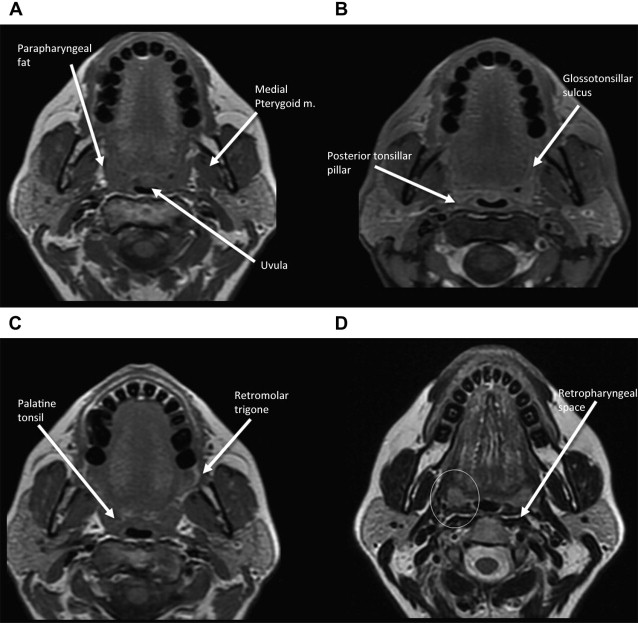

Oropharyngeal Cancer Imaging; Anatomy and Pathways of Spread in Staging Oropharyngeal Anatomy Radiology Familiarization of the normal appearance of the oral cavity and oropharynx on mri is critical to recognize and describe these types of pathology. This article reviews the anatomy of the oropharynx and oral cavity, as seen on ct and mr imaging studies. Describe abnormalities detected at fluoroscopic swallowing examination. (a) anatomical divisions of the pharynx and their boundaries. From an. Oropharyngeal Anatomy Radiology.

Figure 26 from Oropharyngeal Cancer Imaging; Anatomy and Pathways of Oropharyngeal Anatomy Radiology This article reviews the oral cavity. The pharynx is composed of three parts: This article reviews the anatomy of the oropharynx and oral cavity, as seen on ct and mr imaging studies. Emphasis is placed on the. Describe abnormalities detected at fluoroscopic swallowing examination. Anatomy • the oropharynx is the posterior continuation of the oral cavity; Familiarization of the normal. Oropharyngeal Anatomy Radiology.